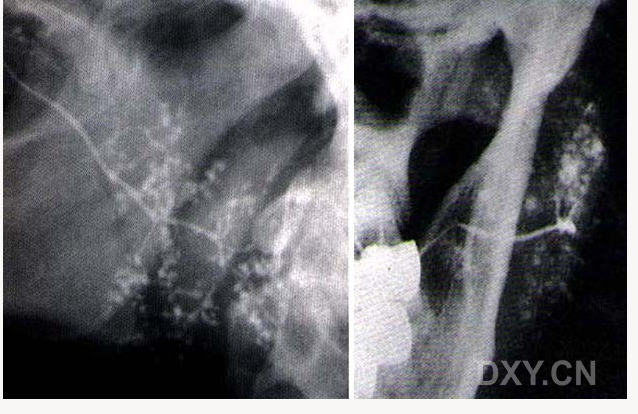

舍格倫綜合征

腺淋巴瘤[沃辛瘤